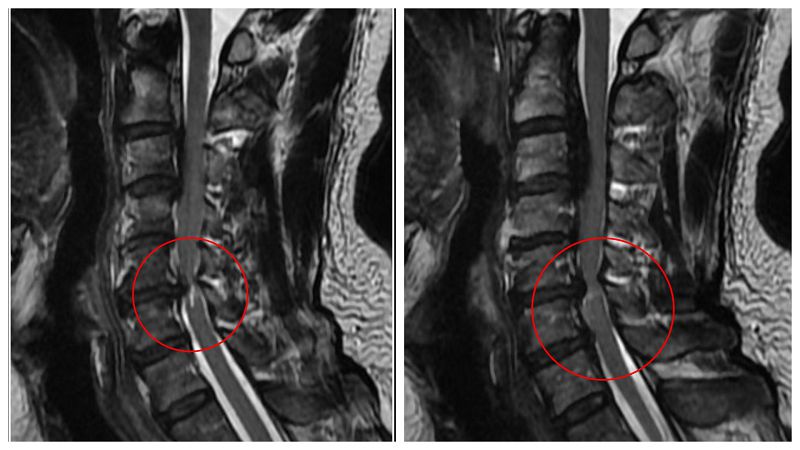

黃先生的頸椎第二節到第六節都有後縱韌帶骨化,其中第五、六節最為嚴重,脊髓已被壓得非常狹窄,核磁共振更可見明顯脊髓空洞,洪祥益主任說,這代表神經已受損,必須盡快手術,若再拖延,一旦跌倒、車禍或頸部突然甩動,都可能造成急性脊髓傷害,增加癱瘓風險。

相較一般骨刺可透過磨除方式處理,後縱韌帶骨化因質地硬且常與硬脊膜緊密沾黏,手術難度與風險顯著提高。洪祥益說明,手術過程需在顯微鏡下精細操作,避免損傷脊髓或造成腦脊髓液滲漏,此外,醫療團隊採取分階段治療策略,第一階段先由前側進行微創手術,直接移除壓迫神經的骨化組織,使脊髓獲得充分減壓;後續再規劃第二階段由後側進行椎板整形術,擴大椎管空間,以降低未來再度壓迫的風險。